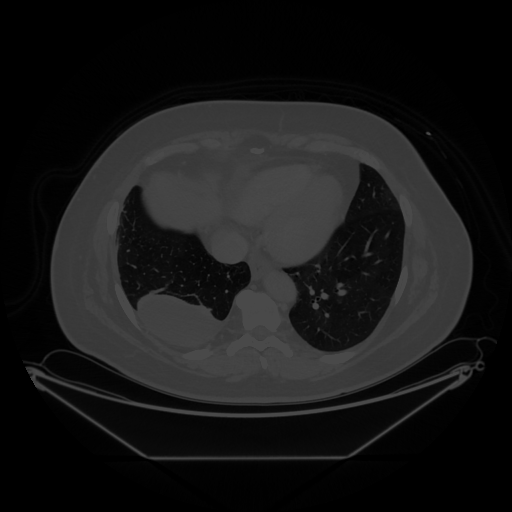

Image Grid

4Γ—3 grid: Rows show different image types (Original NATIVE, Reconstructed NATIVE, Original VENOUS, Generated VENOUS), Columns show windowing techniques (No Window, Lung Window, Mediastinum Window)

Original NATIVE CT scan (input)

No window - Raw intensity values

Lung window (WL -600, WW 1500 β†’ Low βˆ’1350, High +150)

Mediastinum window (WL 40, WW 400 β†’ Low βˆ’160, High +240)